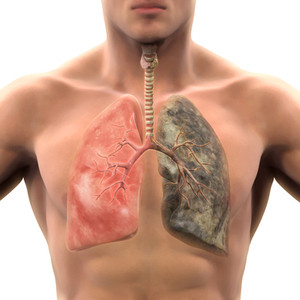

Bronhiālā karcinoma